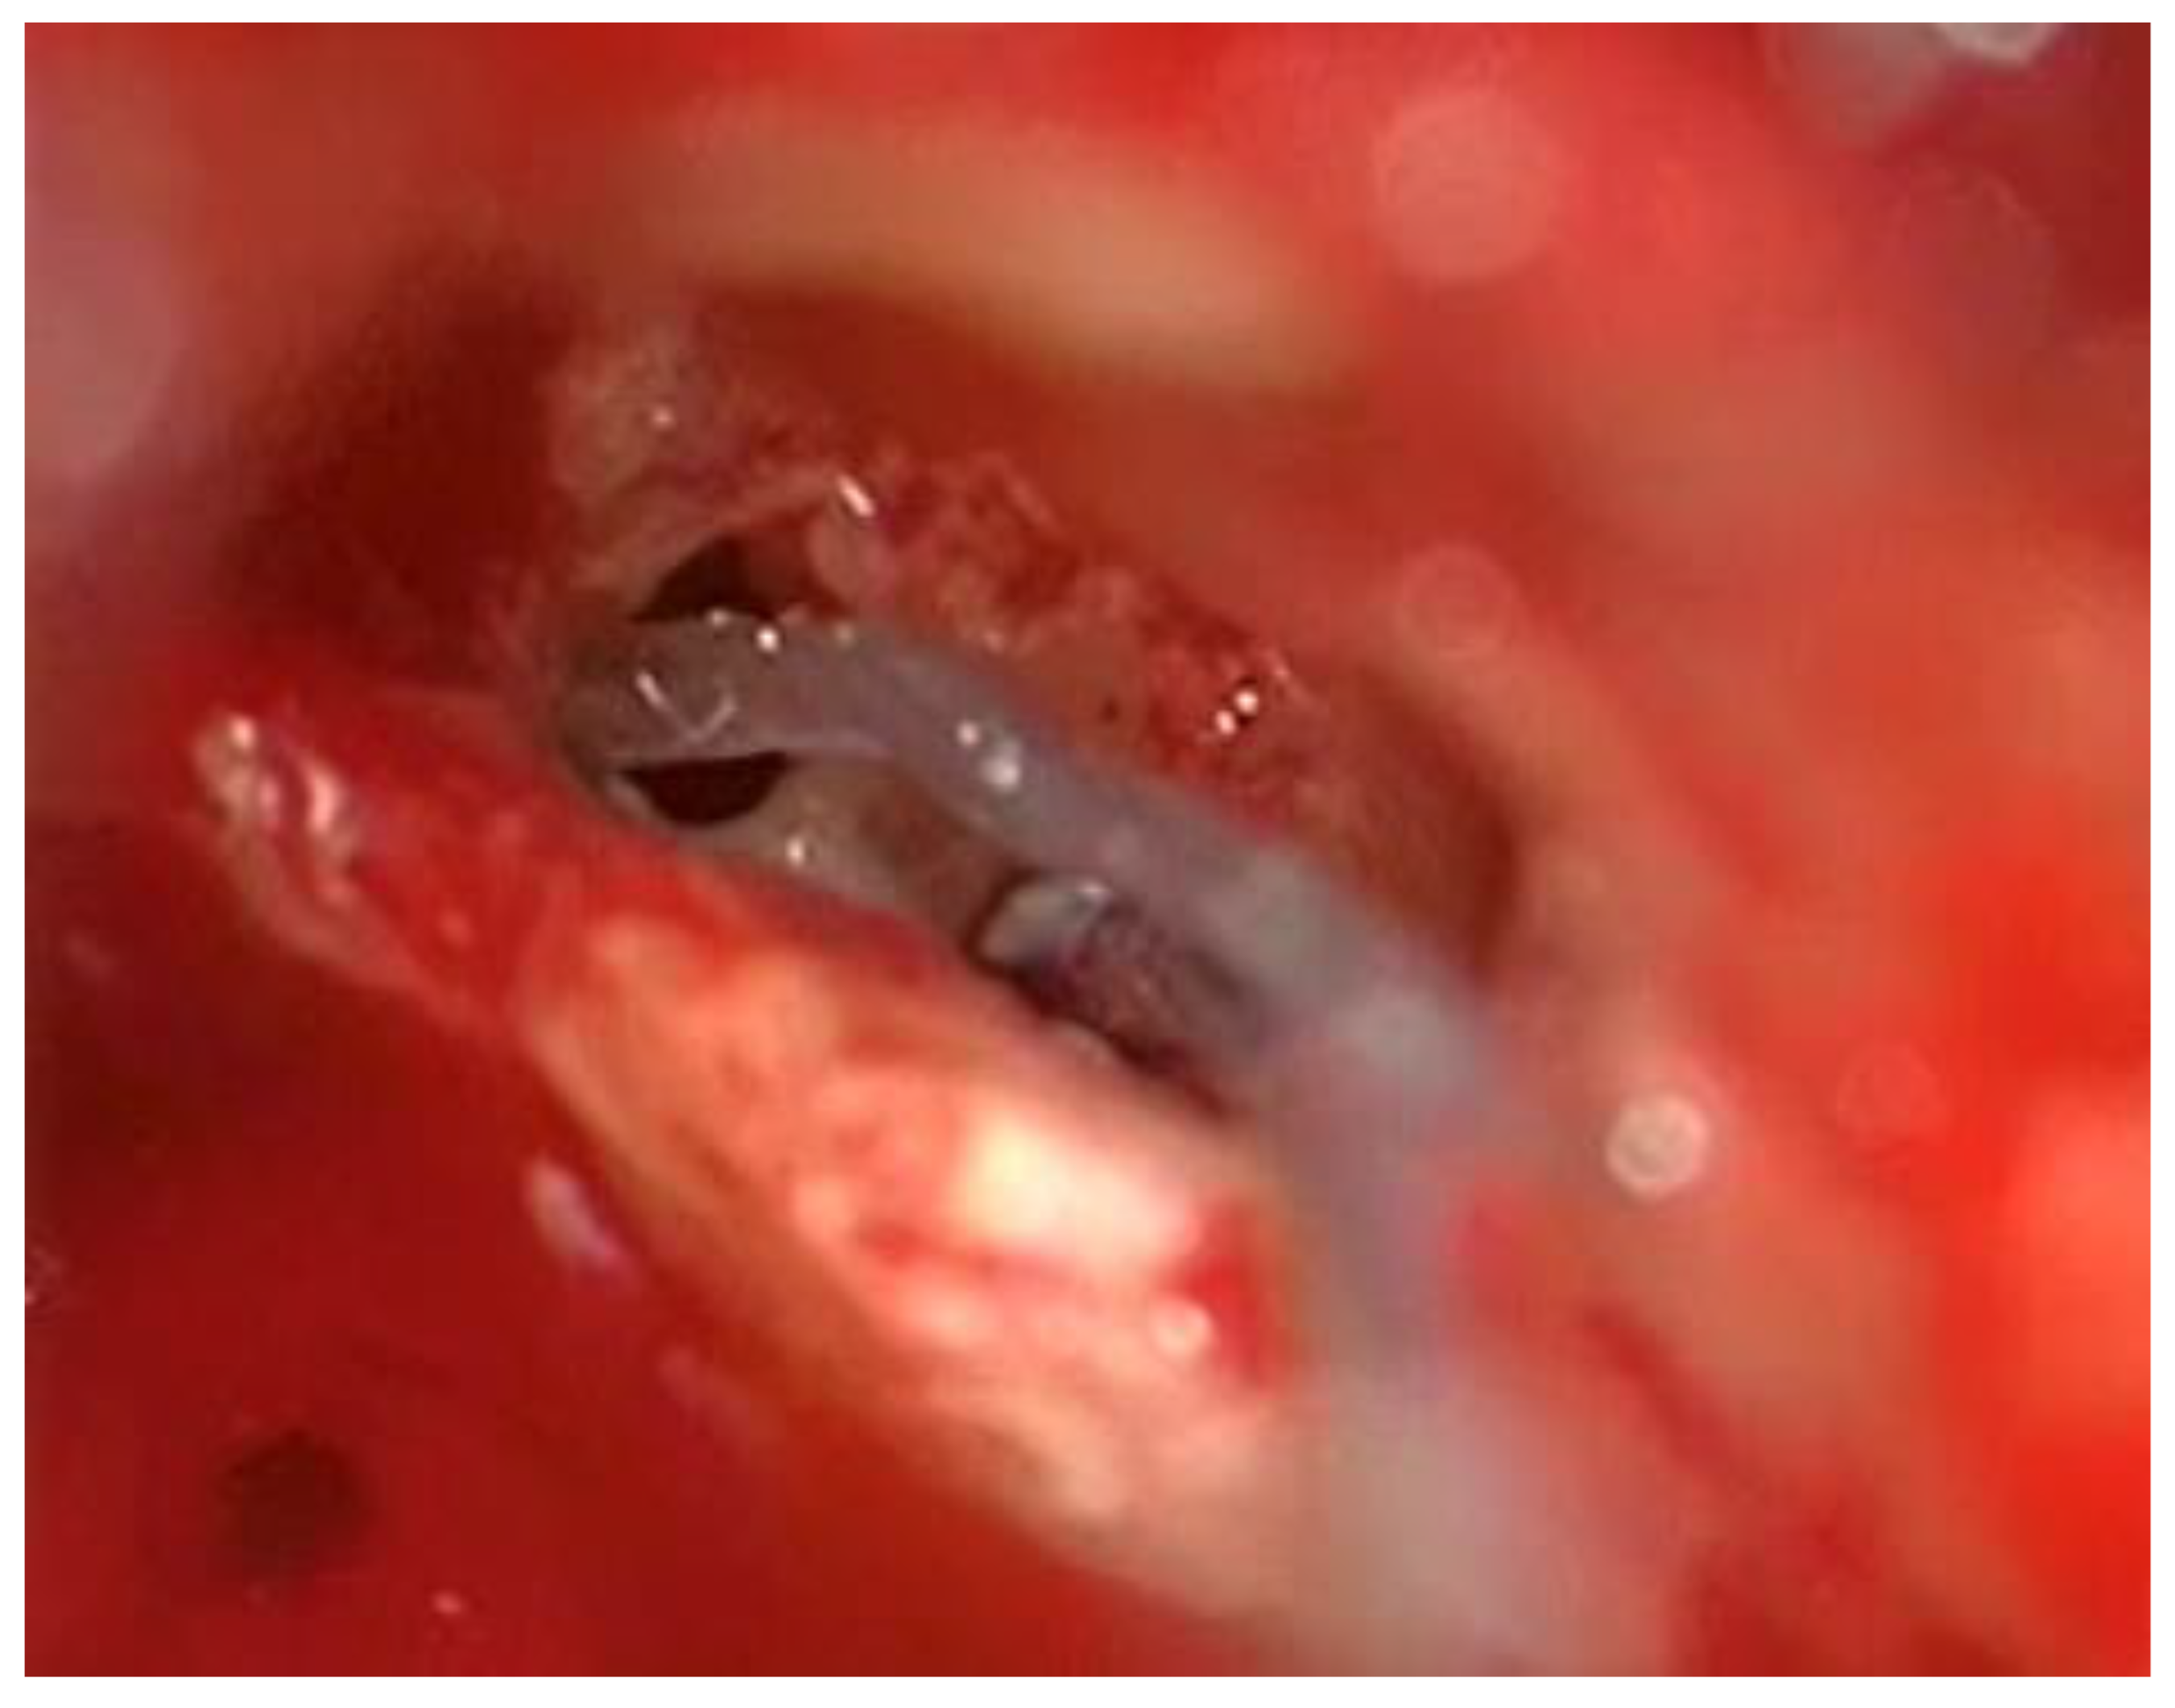

After the removal of parts of the tumor through the enlarged cochleostomy (Figure 1) the TRD was introduced (Figure 2) until the tip was visualized (Figure 3) and carefully grabbed out of the second turn access. By grabbing the tip, the device slipped into the cochleostomy and pushed parts of the tumor out of the second turn. Residual tumor parts could be detached by pipe cleaner handling (Figure 4) and sucked out (Figure 5).

Figure 4. Pipe cleaner handling of the TRD.

Preprints 103791 g004